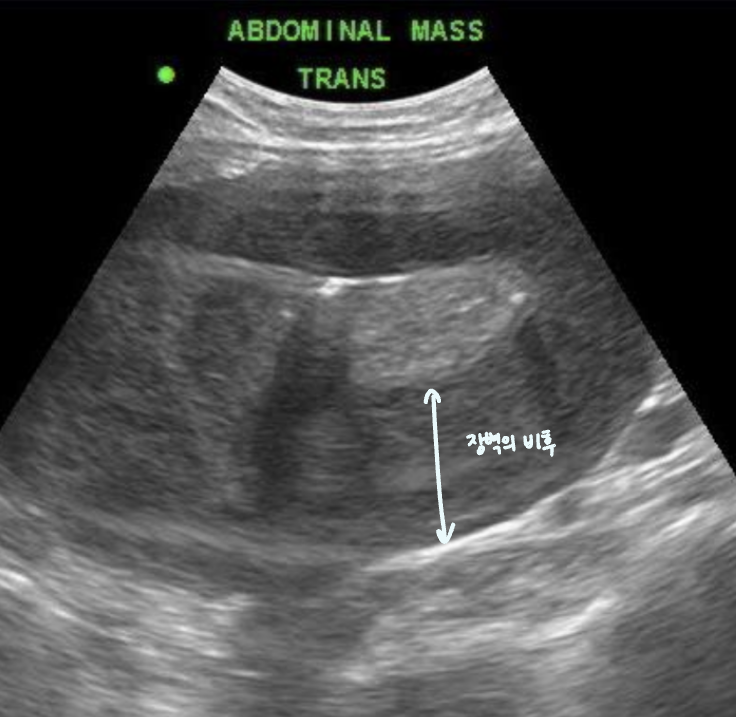

| Stacking sign |

| ์ฅ์ด ์ปค์ ธ์ ์ข์ ๊ณต๊ฐ ์์ ์ฐจ๊ณก์ฐจ๊ณก ์์ด๋ฉฐ ๋ณด์ด๋ sign. |